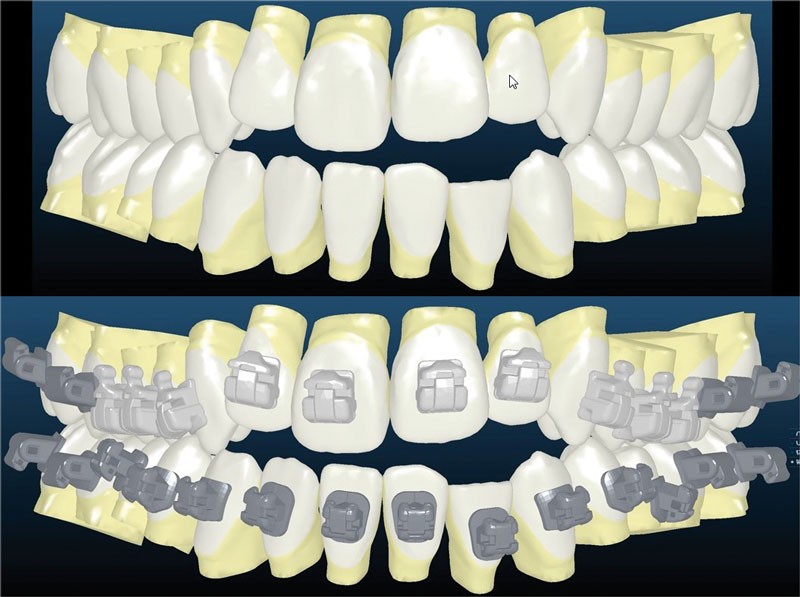

Le set up Insignia

Les empreintes ont été réalisées en sillcone wash technique et adressées au laboratoire Insignia. Actuellement, nous réalisons ces empreintes à l’aide de la caméra intra-orale Lythos et la fiche patient est initialement créée sur la caméra. Le transfert des empreintes au laboratoire est immédiat et le risque d’erreurs considérablement réduit (fig. 4 à 6).